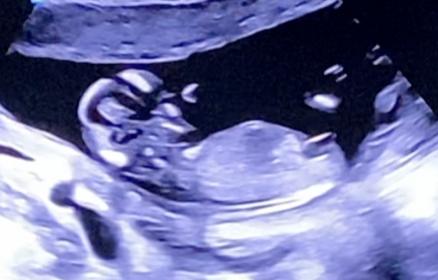

Tricky NUB 13+1 weeks? Long NUB but some stacking?

I had a scan yesterday (13+1 weeks!). During the scan I was convinced I saw long somewhat flat, but also a stacked nub (I saw a shadow in the background), but the tech said it was the stacking was the umbilical cord. The tech said she saw a flat NUB that I is why she was leaning more towards girl.

I posted my scans online and got mostly boy guesses (some girl because of the "flat" NUB) but I was wondering if it's still possible it might be a girl? That the "stacked thing" is something else??? (Already got 3 boys so a girl would be so welcome!)